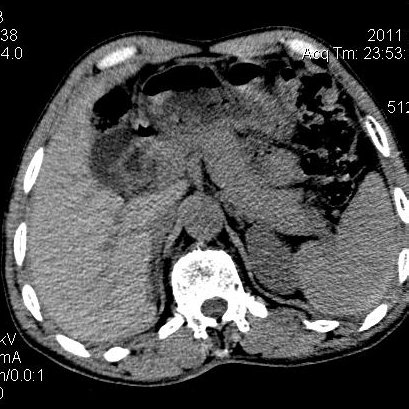

肝左叶发育异常

男性,55岁,骑摩托车摔倒后入院,自述右上腹疼痛

[backcolor=#FF0000]第一次诊断的时候也是这么肯定,可是床旁超声检查并没有发现明显异常,而且患者的一般症状都良好。还好临床只是保守治疗,没有立即手术,第二次复查的时候没有一点变化,又做了MRI检查,没有血肿,

这是一例肝左叶发育异常的,很个性吧~[/backcolor]